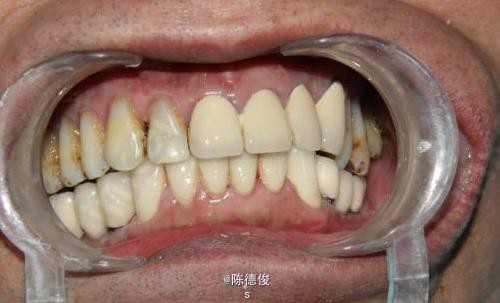

男,64岁,下颌多颗牙缺失数年,身体健康,无烟酒嗜好。

诊断:肯氏1类缺失 诊疗方案:种植固定桥修复+咬合重建 种植系统:瑞士ITI-Straumann种植系统 治疗周期:3个月